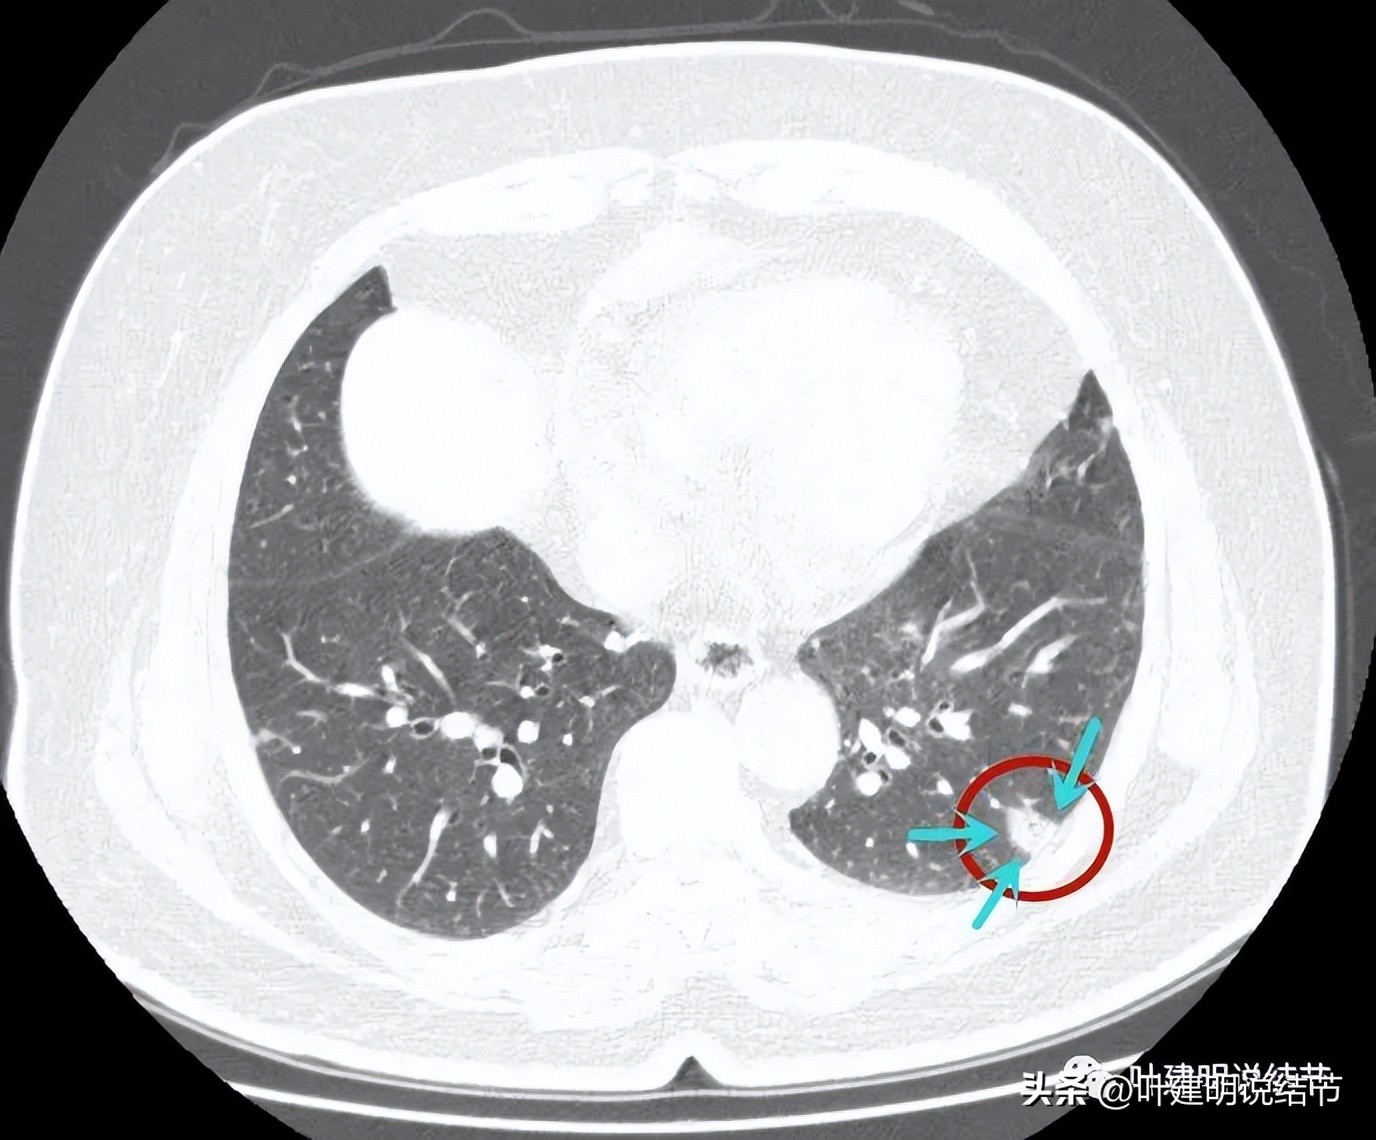

病灶密度整体较高

边缘部分

冠状位显示病灶不是很密实,表面是不平的,但毛刺略偏长,收缩力不够

整体缺乏膨胀感